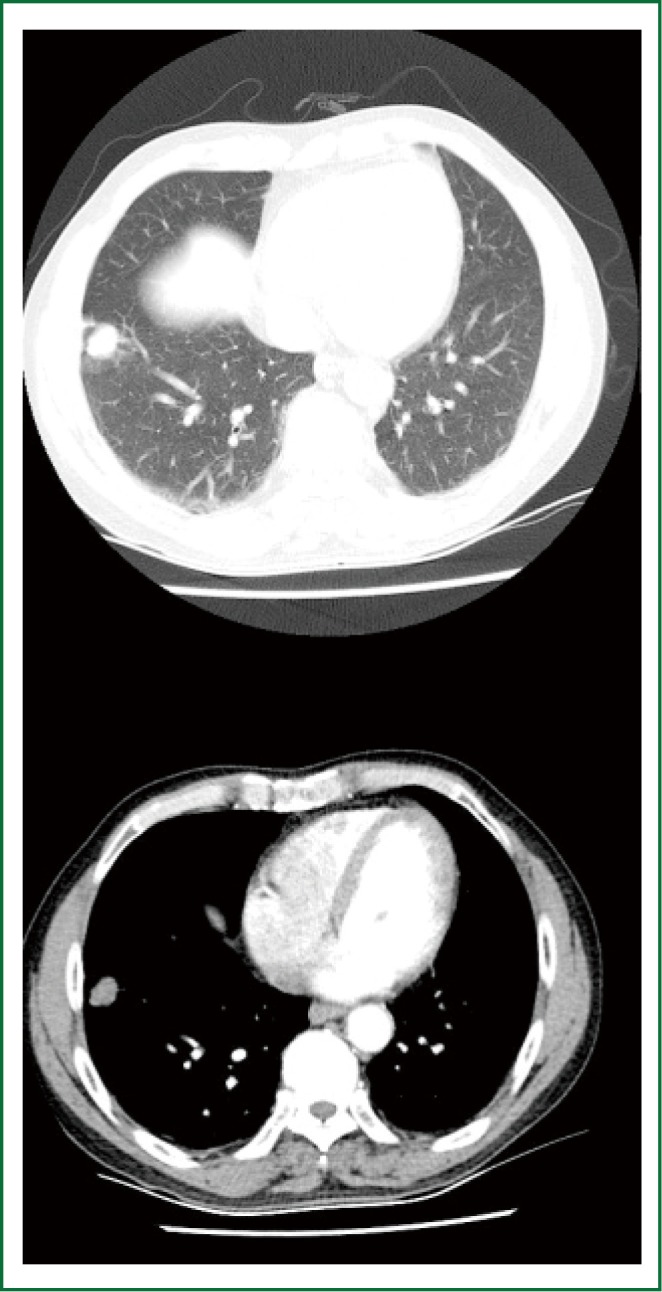

This 68-year-old male patient had a 40-year history of smoking, although he had no history of other major diseases. He was presented for the persistent cough for over one year. PET/CT prompted that there was a lesion of about 23 mm × 18 mm at the basal segment of right lower lobe of lung (Figure 1), with a maximal SUV value of 9.3. Subcarinal and upper mediastinal lymph nodes were displayed. However, the radioactivity uptake of the mediastinal lymph nodes was not remarkably increased. No metastatic lesion was found. Preoperative pulmonary function tests prompted FEV1 2.26 L (74.1% predicted), FVC 2.92 L (76.4% predicted), and FEV1/FVC 77.31%.

Figure 1.

Chest CT indicated a nodule at the right lower lobe, together with pleural traction sign. Lung cancer was considered.